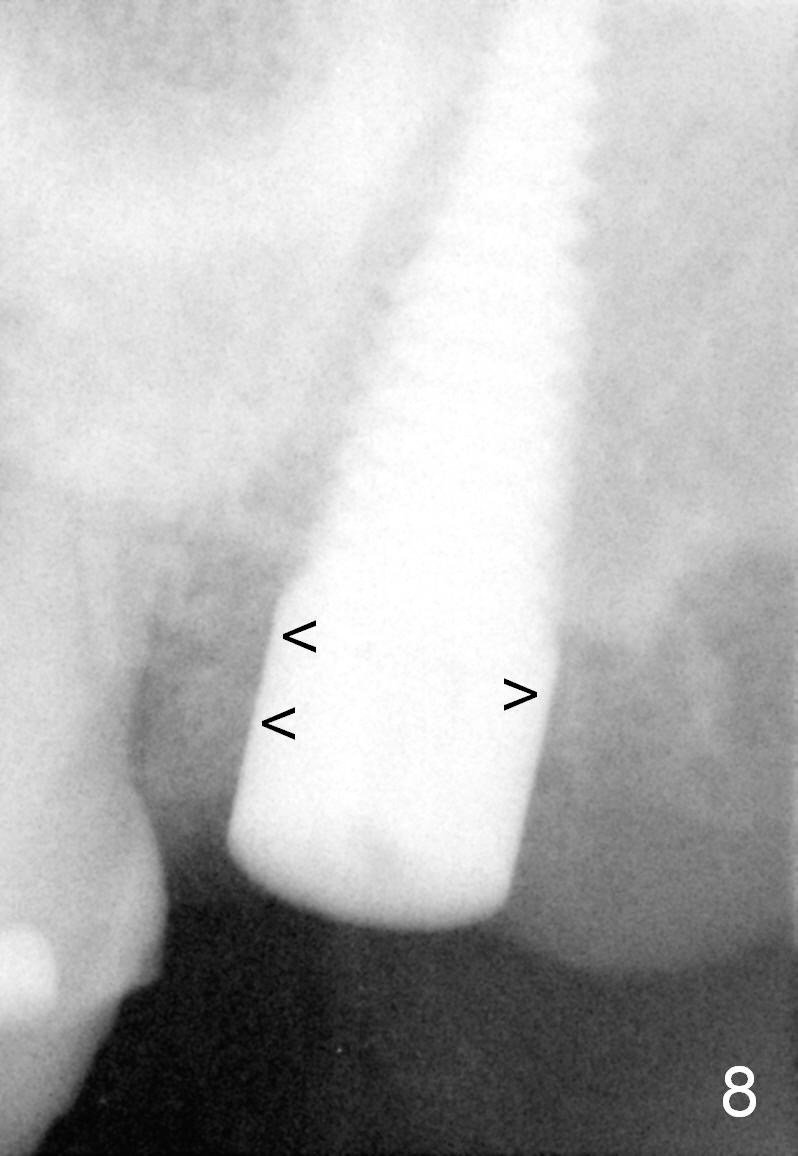

A 57-year-old lady presents for abscess buccal to the tooth #15 (Fig.1 A). Mesial and distal to the occlusal composite (Fig.2 C) is a crack line. In addition to long furcated roots, the upper border of the bone is not shown in this preop PA (arrow). Fig.3 is taken to show a thin septum surrounded by the mesiobuccal (MB), distobuccal (DB) and palatal (P) sockets (Fig.3). Osteotomy is initiated in the septum by 1.2 and 1.5 mm pilot drills, followed by 2,3,4 mm rounded tapered osteotomy at the depth of 17 mm. Nose blowing test is carried out after each step with negative result. Stability is achieved when a 4.5 mm tap is inserted at 17 mm, but the upper end of the tap is not visible (Fig.4,5). When a 5 mm tap is placed, stability is decreased, probably because the coronal end of the septum starts to break down (due to expansion). To re-gain stability, the 5 mm tap needs to go deeper. A 6 mm tap also achieves satisfactory stability at 20 mm. When the tap is removed, there is no air leakage. A 6x20 mm implant is placed with insertion torque > 60 Ncm; the upper end of the implant is still out of view in PA (Fig.6). Another problem is that the implant needs to go deeper to obtain sufficient occlusal clearance. The lower first molars and the 2nd premolars are missing. A panoramic X-ray has to be taken to show the apical end of the implant: ~ 3 mm into the sinus (Fig.7 ^). The maxillary tuberosity appears to grow downward (arrow). In other word, the tooth #15 appears to have been intruded due to overloading.

The mesial and distal socket spaces apparently disappears 3 months postop (Fig.8).